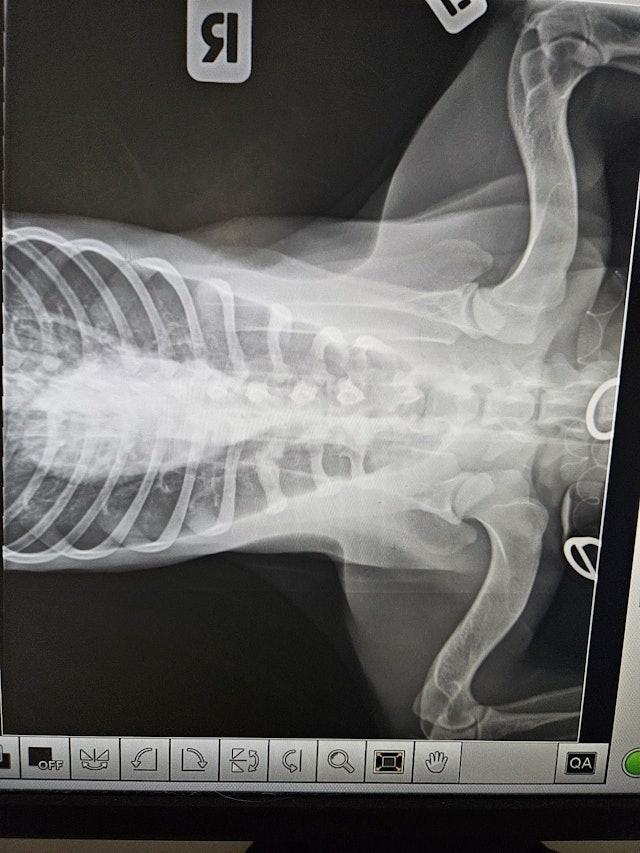

元朗日前發生一宗有狗隻懷疑被車輛撞到後死亡事件。一隻黑色唐狗,於周二(12日)晚上11時許,在元朗大馬路近元朗廣場對開,懷疑被一輛巴士撞倒,涉事車輛未有停下,狗隻則自行爬回行人路。有途人見狀通知動物義工協助並報案,惟未能確定該巴士的車牌或路線等。義工帶同狗隻前往診所搶救,發現其陰囊被撞爆、睪丸跌出。經手術後情況雖一度好轉,惟於翌日凌晨離逝。